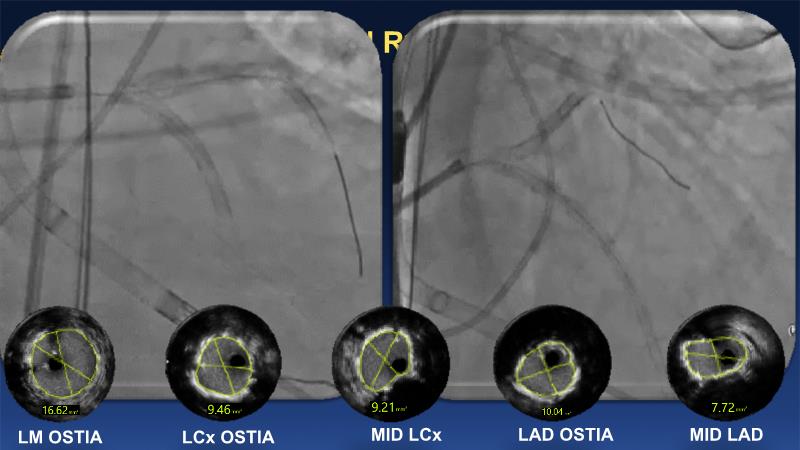

Over the last five years, we have learned that there is a new tool for treating calcium, the greatest enemy of interventional cardiology, which can take various forms: intravascular lithotripsy. In this session, look at how to master this technique in different scenarios, from eccentric calcified lesions to left main bifurcations.

- To understand the mechanism of action of intravascular lithotripsy (IVL) for the treatment of calcified lesions

- To uncover practical tips and techniques for IVL in challenging calcified lesions: eccentric calcified lesions

- To learn how to safely utilise IVL in left main bifurcations